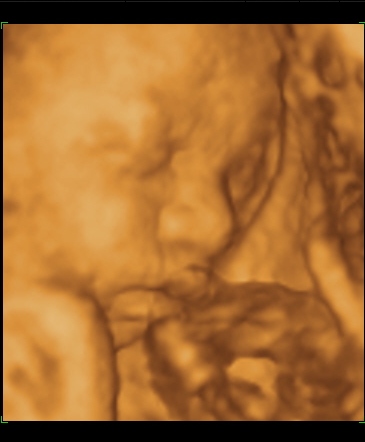

Cscsi:Nagyon aranyos a kis fiad!!És nagyon tündéri a pici babóca is!!!Azt hittem, hogy csak a leányzók tudnak lustizni, de ezek szerint tévedtem!!!A mi pici Leányzónk is, a legutóbbi 4D-n szunyált, és a kis pofiját a méhlepénybe fúrta!!De mi a végén feltudtuk a kis Mazsolát ébreszteni, és sikerült pár jó képet csinálni róla!